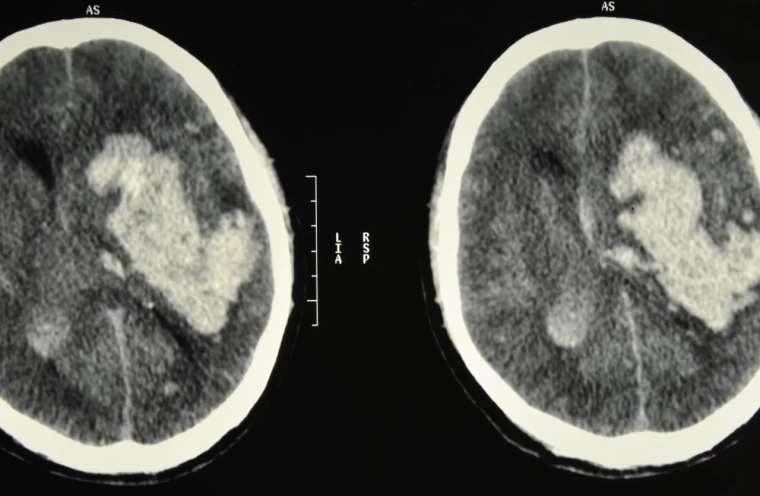

Beyin kanaması, aniden gelişen ciddi bir tıbbi durumdur ve beynin içerisindeki kan damarlarının patlaması sonucu meydana gelir. Bu durum, beynin normal fonksiyonlarını bozan bir basınca yol açar. Genellikle bir travma veya yüksek tansiyon gibi sebeplerden kaynaklanan beyin kanaması, anında müdahale gerektiren ve ölümcül sonuçlar doğurabilecek bir durumdur. Beyin kanamasının belirtilerini ve nasıl anlaşılabileceğini anlamak, erken müdahale şansını artırır. Bu yazıda, beyin kanaması belirtileri ve bu durumun risk faktörleri hakkında detaylı bilgi vereceğiz.

Beyin kanaması, hemen her zaman tehlikelidir, ancak bazı durumlarda daha büyük riskler taşır. Özellikle kanamanın büyük olduğu ve beyin dokusuna ciddi baskı yaptığı durumlar son derece tehlikelidir. Kanamanın gerçekleştiği bölge de önemlidir. Beynin hayati fonksiyonları kontrol eden bölgelerinde meydana gelen kanamalar, solunum durması, kalp atışı düzensizliği ve bilinç kaybı gibi ölümcül sonuçlara yol açabilir. Eğer beyin kanaması erken fark edilmez ve tıbbi müdahale gecikirse, kalıcı beyin hasarları veya ölüm riski artar.

Beyin kanamasının ilk belirtileri, kanamanın yerine ve şiddetine bağlı olarak değişir. Ancak genel olarak, ani ve şiddetli baş ağrısı en yaygın belirtidir. Bunun yanında bulantı, kusma, görme bozuklukları, konuşma zorluğu, denge kaybı, yüz veya vücutta ani uyuşma ve bilinç bulanıklığı da görülebilir. Bu belirtiler, özellikle ani ve beklenmedik bir şekilde ortaya çıkıyorsa, derhal acil tıbbi yardım alınmalıdır. Zamanında müdahale, beyin kanamasının yol açabileceği kalıcı hasarların önlenmesinde kritik rol oynar.